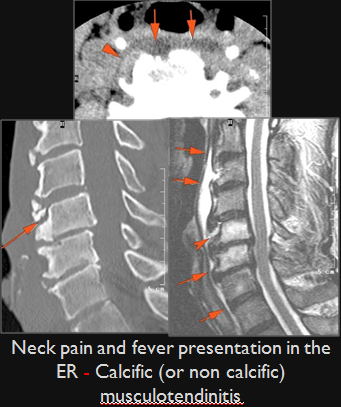

Prevertebral and Epidural Spaces

There is edema/abscess within in the prevertebral or paravertebral spaces. [Yes/No]

There is erosive process involving the disc spaces or other components of the spine. [Yes/No]

Prevertebral abscess, discitis and/or epidural abscess.

Prevertebral musculotendonitis